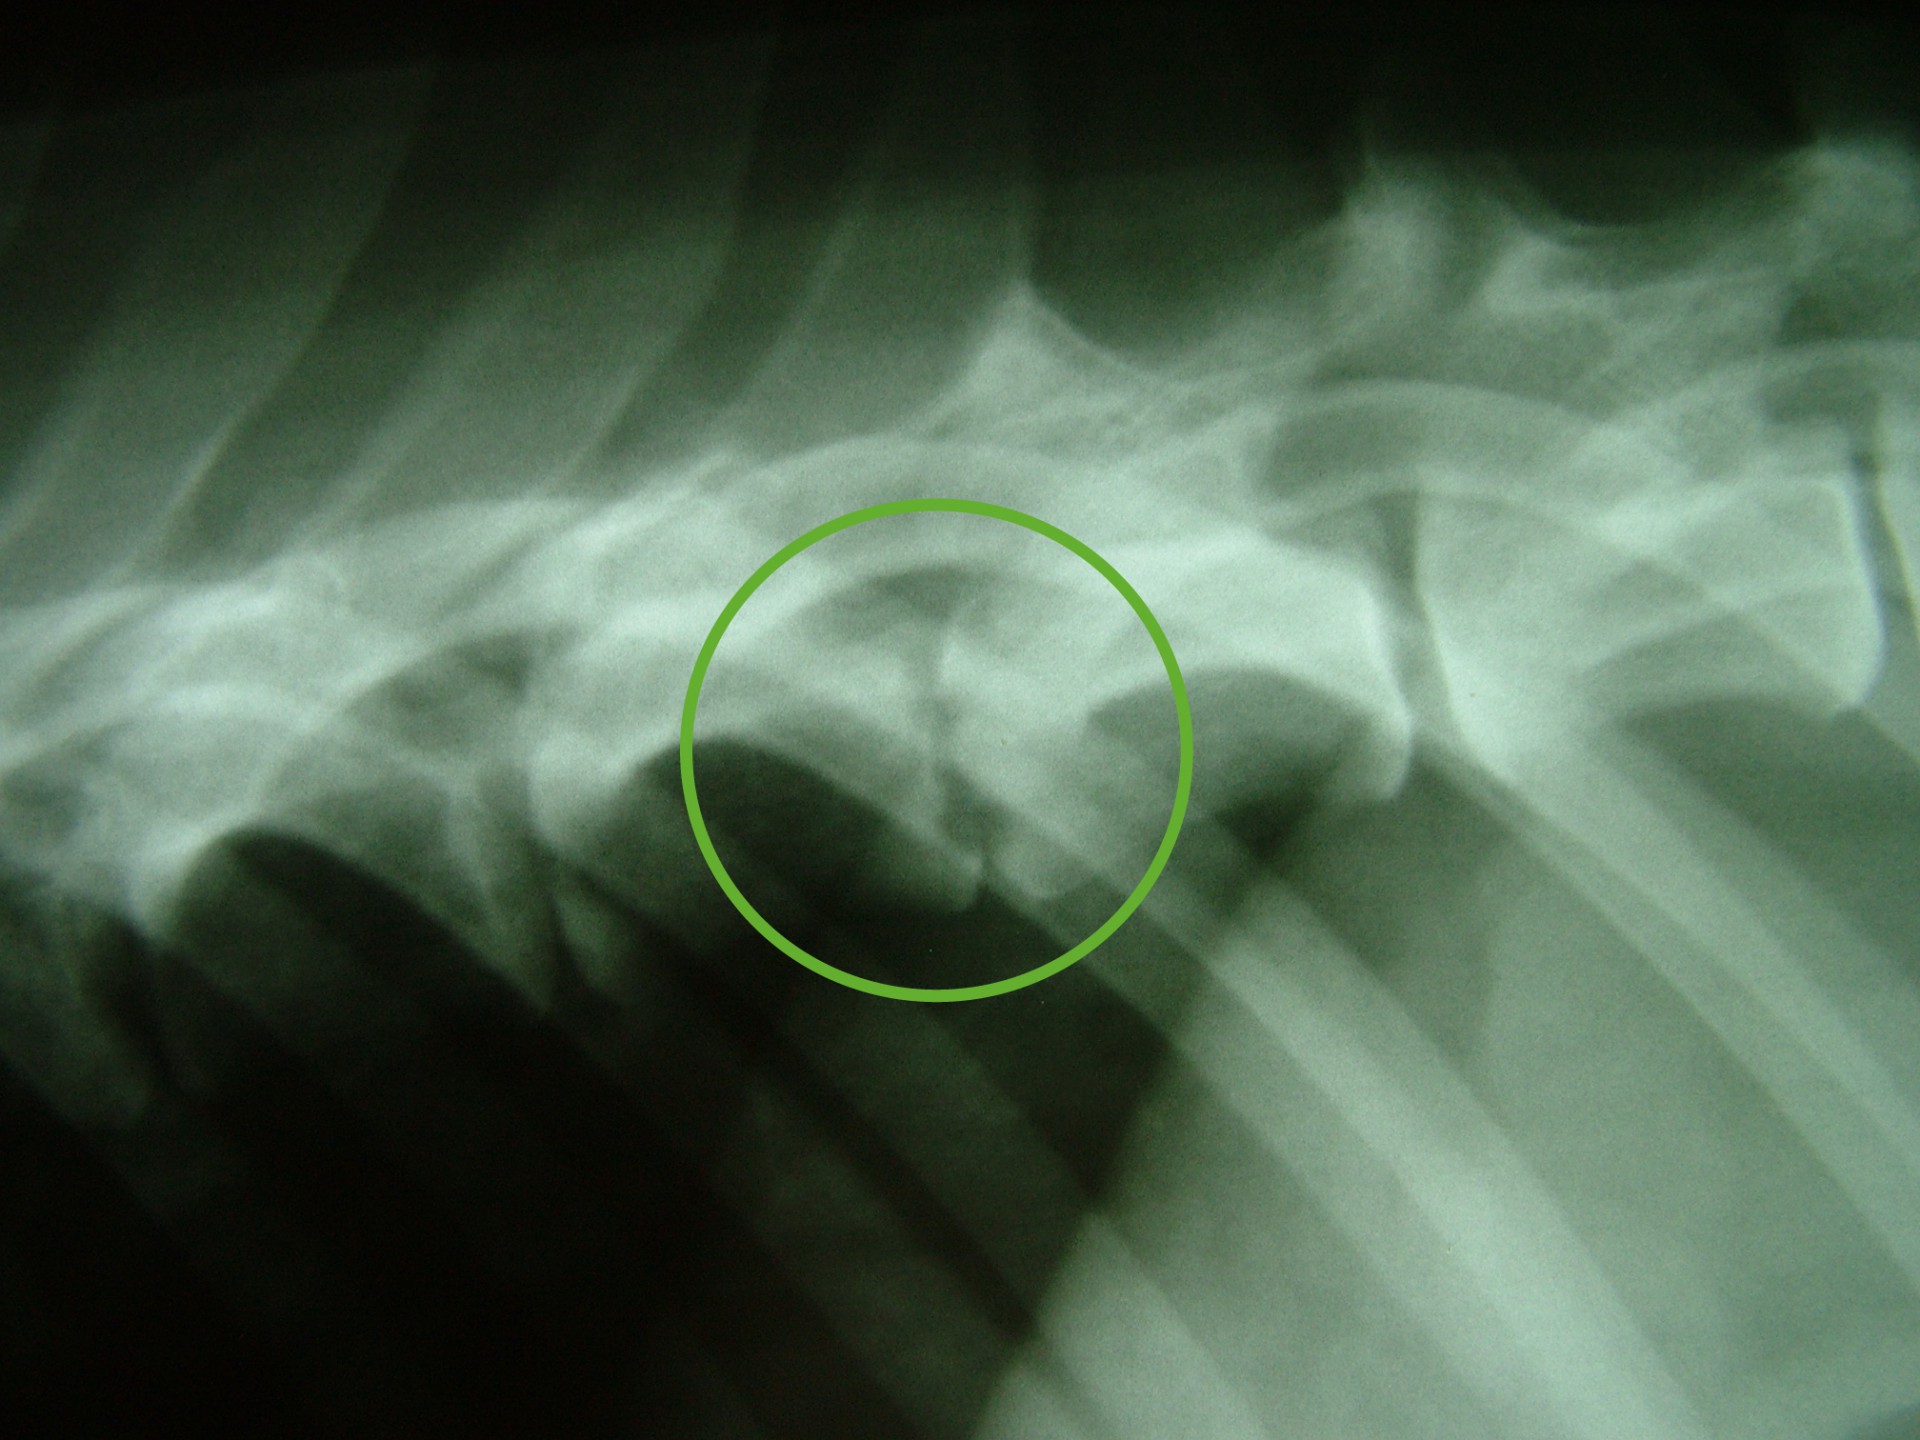

Szürke Farkas a 9 éves husky keverék kutya 4 napos csavargás után érkezett haza. Gazdája konstatálta, hogy a bal hátsó lábára sántít, így elhozta rendelőnkbe, ahol egy alapos vizsgálat után – mely során érdembeli elváltozást nem találtunk- fájdalomcsillapítókat adtunk neki és haza engedtük. Néhány nap után gazdája jelezte, hogy a kutya állapota nemhogy javulna, rosszabbodik. A kifejezett gerinctájéki fájdalmasság miatt myelographiát( gerincfestést) javasoltunk, mely során az utolsó ágyék és első keresztcsonti csigolya magasságában gerincvelő összenyomatást diagnosztizáltunk ( ld.: caudaequinacompressio). A sikeres műtétet követően néhány napon belül a fájdalom enyhült, együtt örültünk a gazdival.

Ám az öröm nem tartott sokáig. Szürke Farkas 5 nappal a műtéte után a kocsiba ugrás közben felsírt és mire a rendelőbe ért a fájdalomtól fel sem tudott állni. A kórházi felvételt követően fájdalomcsillapítók, antibiotikumok adását kezdtük meg és mivel a műtéti területen klinikai és RTG vizsgálattal sem találtunk a fájdalmat magyarázó elváltozást Kaposvárra, MRI vizsgálatra vittük. 2 nappal később meglepődve olvastuk az eredményt: a 9.-10.( Th9-Th10 ) hátcsigolyák valamint a 7 ágyéki és az 1. keresztcsonti csigolyák ( L7-S1 ) közötti porckorong gyulladásos elváltozása ( ld.: discospondylitis ) mellett a 11. és a 12. hátcsigolya magasságában ( Th 11-Th12 ) a gerincvelőt összenyomó daganatos elváltozás volt látható. Mivel a porckorongok gyulladása megmagyarázta a gerinctájéki fájdalmasságot, annak kezelése és a fájdalom további csillapítása volt az első teendőnk. Néhány nappal a fájdalom enyhülését követően a gerincvelőt összenyomó daganatot műtétileg eltávolítottuk. Ezt követően Szürke Farkas még további 60 napot töltött a kórházban. A lábadozása napról napra szépen alakult. Betegségének 90. napján hazaadtuk és a gyógyszerek további adása mellett állapotát hetente ellenőriztük.